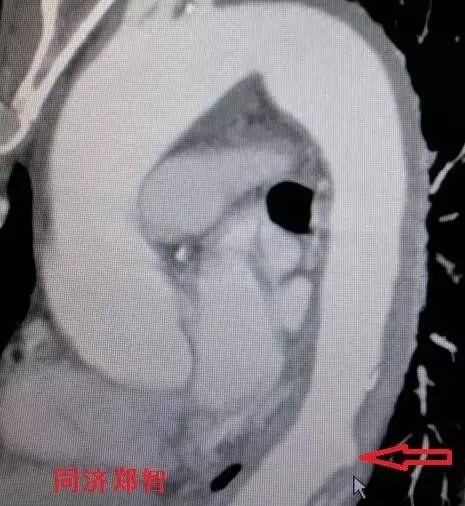

① Stanford B型 主动脉壁间血肿的CTA重建(图1),提示胸降主动脉以远的主动脉壁病变(红箭头所示)。

图1